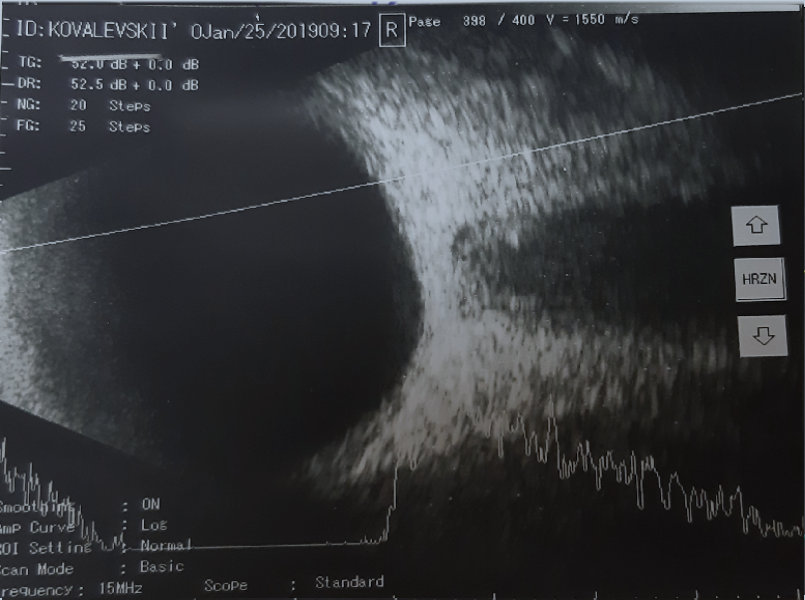

Рис. 7. A- и B-сканирование пациента К. при первичном обращении. В-скан: аксиальная горизонтальная проекция, умеренное количество помутнений в стекловидном теле. А-скан: 9 эхопиков средней и низкой эхогенности

Fig. 7. Initial treatment, Patient K.: B-scan: axial horizontal projection, moderate amount of “clouding” in the vitreous body. A-scan: 9 peaks of medium and low echogenicity